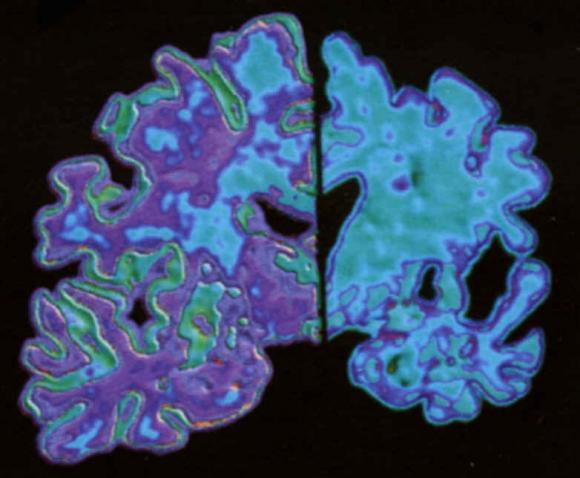

Ambos expertos señalan la importancia de realizar pruebas que puedan detectar la enfermedad en fase temprana. Una de las opciones que se barajan es el desarrollo de bioquímicos, por ejemplo de la proteína del amiloide, o una resonancia magnética que permita conocer si, el patrón de atrofia del cerebro es típico de Alzheimer. De este modo, podría realizarse un diagnóstico aún cuando la persona está realizando una vida normal, siendo éste el momento perfecto para empezar el tratamiento.